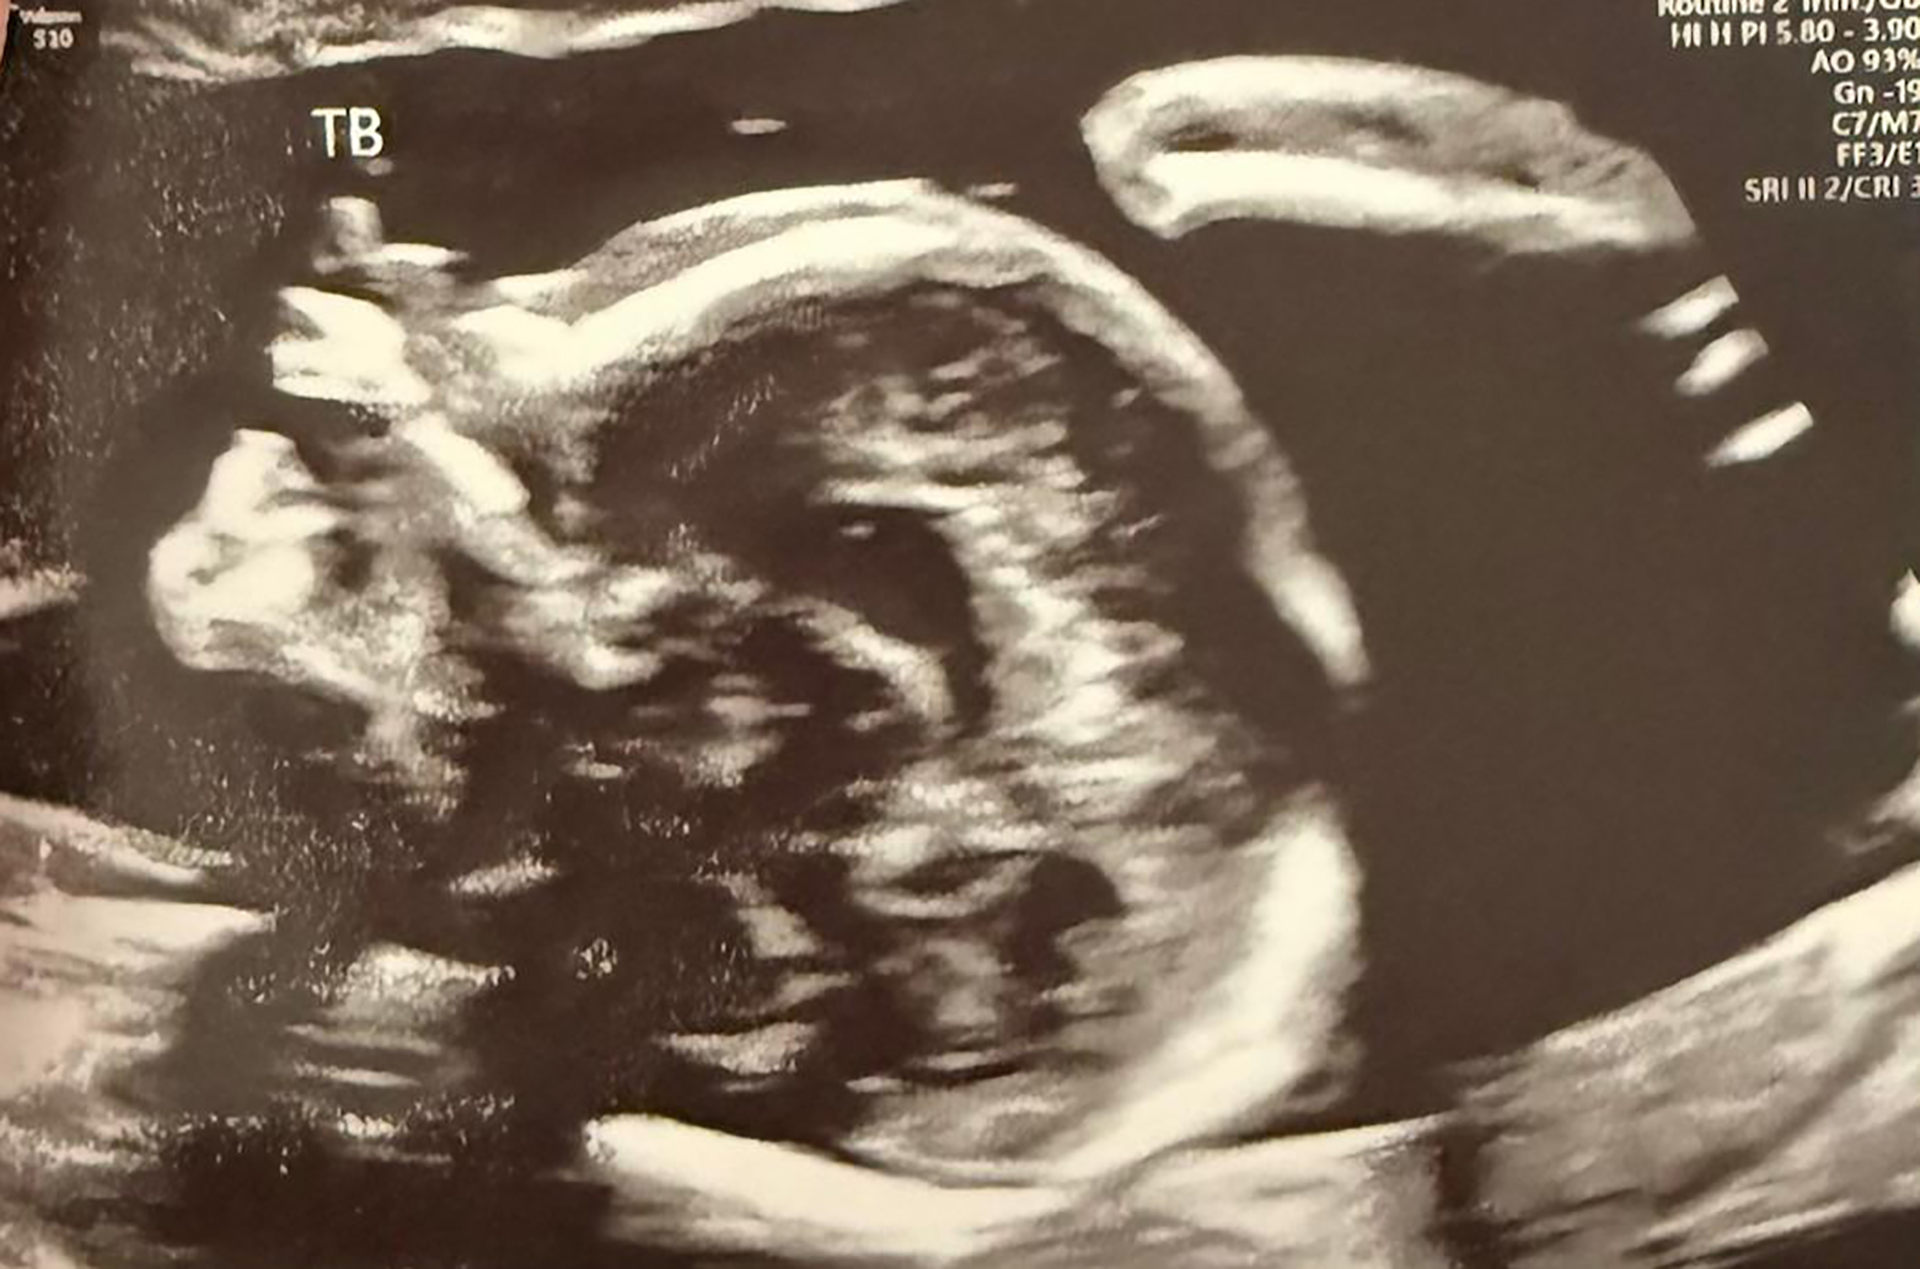

At the following scan, which happened to be our 6th wedding anniversary, Dr Janice suddenly said, “Oh my God.” I panicked, thinking something was wrong. Then she said, “There are three.” One embryo had split. That was how we found out we were expecting triplets.